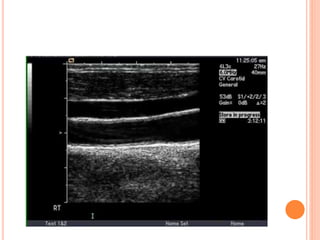

 There are no widely accepted duplex criteria for the

diagnosis of vertebral artery stenosis. Some have used a

peak systolic velocity of >100 cm/sec to diagnose a

stenosis >50%. Bi-derectional flow could mean a high

grade stenosis

 A problem with ultrasound for the vertebral arteries is that

the stenosis is often at the origin and this cannot be seen

in many cases